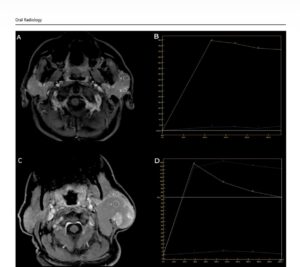

Образните изследвания – компютърна томография и мултипараметрична магнитнорезонансна томография – разкриват характерни особености на тумора. На MRI се установява специфична комбинация от находки: силно понижен сигнал на определени последователности („signal void“), повишен сигнал на T1-претеглени изображения и минимално контрастно усилване на кистозните части на лезията, като усилване се наблюдава основно в папиларните структури. При двата случая е установено изместване,

но не и инфилтрация на лицевия нерв – ключова информация за безопасното хирургично лечение.